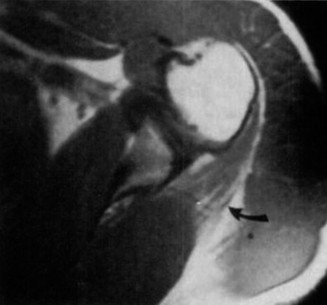

The correct answer is (B). An MRI showing a rotator cuff tear is considered diagnostic of a rotator cuff tear because of its high sensitivity, specificity, and accuracy. It has superb soft tissue imaging abilities (see Fig. 2–5). However, it should be noted that while MRI usually can differentiate between partial- and full-thickness rotator cuff tears, this varies with the power and accuracy of the MRI facility. This is also true with the ability of MRI to differentiate between partial-thickness rotator cuff tears and subacromial bursitis. An arthroscopy is needed for definitive differentiation of these pathologies.

Figure 2–5_Coronal oblique view MRI slice of a left shoulder. (Reproduced with permission from Smithius R and van de Woude HJ. Shoulder MR Anatomy: Normal Anatomy, Variants, and Checklist. _Radiology Assistant. April 2, 2012.)

Figure 2–8_Reproduced with permission from Stadnick ME. _Partial Rotator Cuff Tears. MRI Web Clinic. 2007 (Apr).

The correct answer is (A). These are best diagnosed on an MRI as seen in the imaging provided; addition of intra-articular contrast can further improve this study. Answer B, full-thickness rotator cuff tear, is incorrect as the bursal side of the tendon can be seen to be in continuity. Answer C, a SLAP lesion, will be visualized as a labral tear on a coronal MRI and will be found at the biceps root. Answer D, an ALPSA lesion, will be most clearly seen on an axial MRI. It is a variant of a Bankart lesion where the labrum is displaced medially and inferiorly rolling down the glenoid neck underneath the periosteum.

MRI remains the most popular imaging modality for diagnosing rotator cuff tears. Normal rotator cuff tendon appears dark on both T1 and T2 sequences. Tears may be noted as being full-thickness, articular-sided, bursal-sided, or intrasubstance. They are visualized as a disruption in the regular contour of the tendon and increased signal intensity on T2 sequences. Occasionally, an MR arthrogram may provide additional information regarding a cuff tear, although this is not routinely ordered.